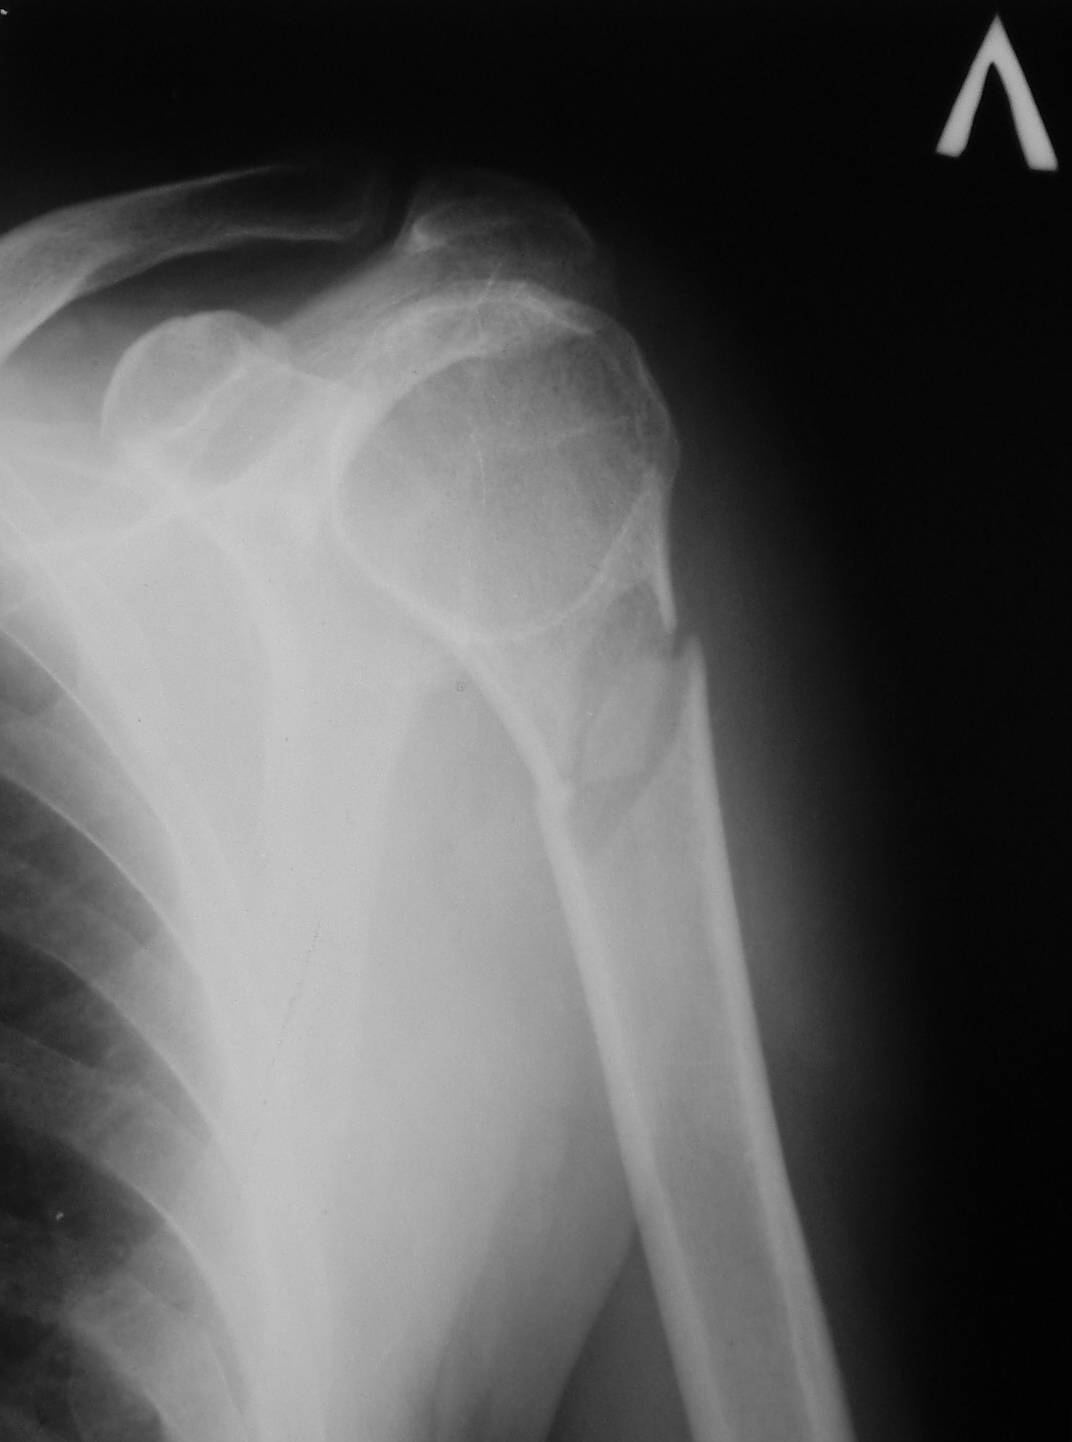

Рентгенологически патологический перелом шейки левой плечевой кости,

Обычный перелом с адекватным механизмом.

наличие секвестра,

Где Вы видите секвестр и что под этим термином подразумеваете? Может быть Вы имеете ввиду небольшой (2х1,5 см) отломок?

шаровидная полость в головке.

Это не шаровидная полость, а нормальное рентгеновское изображение ротированного проксимального отломка

Сегодня сделал контрольный снимок места перелома и дествительно отломок, который я принял за секвестр изменился, хотя полость возможной кисты сохраняется. Спорным остается наличие шарополости в головке плеча. Сделал также и противоположный сустав для сравнения. Возможности КТ в моей ЦРБ не имеется. В обласной центр ( 100 км. ) потерпевший ехать не очень стремится.

Данная полость на стороне поражения очень напоминает полость аневризмальной кисти. Кто нибудь втречал такую патологию у взросхих?

Это не полость и не секвестр. Остеопороз головки плечевой кости и фрагмент.С противоположной стороны (другая проекция)также зона остеопороза в области большого бугорка.

Дифференциальную диагностику надо проводить между однокамерной костной и аневризмальной кистой, но расположение в полости кисты тонкого,

линейного фрагмента кости, подтверждает диагноз однокамерной костной кисты.

"Упавший" фрагмент - патогномоническая подсказка к патологическому перелому, часть стенки падает в полость кисты и опускается вниз из-за

силы тяжести.

Подозрение о "шаровидной полости" в головке - это из-за укладки, и на представленном снимке подтверждение правильности рекомендации коллег.